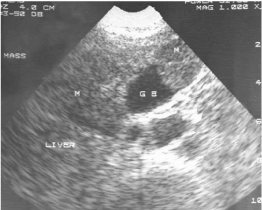

Ultrasound of the patient revealed a mass of mixed echogenicity arising from the anterior wall of the gall bladder (GB) and invading the liver (Figure 1). Another mass predominantly hypoechoic with non-homogenous internal echoes was found in proximity to the first mass, in right lobe of liver. Computed tomography showed a polypoidal mass arising from the anterior wall of the GB and protruding into the lumen (Figure 2). Mass was also extending into the adjacent area of the liver. On the right side of the GB, another focal mass of variegated appearance was seen. A probable diagnosis of carcinoma of the gall-bladder with a secondary in liver was suggested.

Figure 2. CT picture showing a polypoidal mass arising from anterior wall of GB and protruding into the lumen (long arrow). Another focal mass of variegated appearance also seen (short arrow)